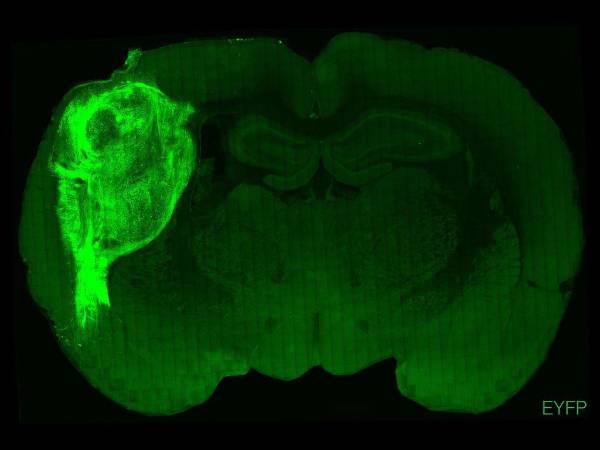

Neurogénesis es un tema muy debatido en la comunidad científica.

Investigación

¿Hasta qué edad sigue formando neuronas el cerebro?

Un nuevo estudio confirma que "hay una formación continua de neuronas en el hipocampo del cerebro adulto", lo que aporta nuevas pruebas para ampliar otras investigaciones